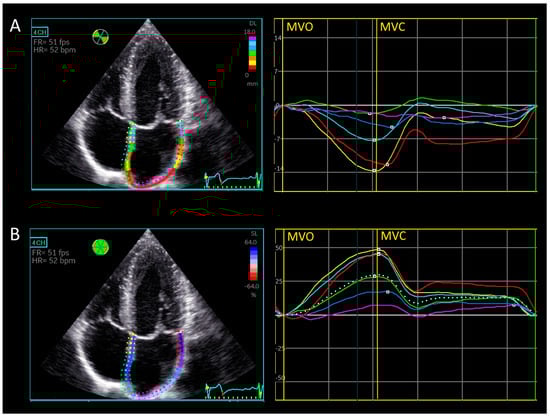

2.2.1. Automatic Biplane Method for Left Atrial Strain [15]

2.2.2. Manual Triplane Left Atrial Strain Assessment Using Ventricular-Dedicated 2D Strain Software

2.2.3. Left Atrial Walls and Segment Definitions for Regional Strain Calculation

2.2.4. Longitudinal Displacement

3.3. Longitudinal Displacement

3.4. Left Atrial Wall Motion Analysis